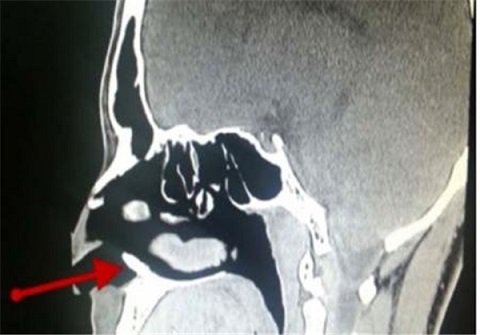

سیمرغ - یک پسر 22 ساله اهل عربستان سعودی بیش از حد و به طور مکرر دچار خونریزی بینی می‌شد که به همین دلیل به دکتر مراجعه کرد؛ پزشک با عکس انداختن از بینی وی متوجه شد یک استخوان سفید رنگ در بینی وی در حال رشد است؛ در واقع یک دندان اضافی به طول 1 سانتی‌متر در بینی وی رشد کرده بود.

پزشکان گفتند این خونریزی ناشی از دندان در بینی وی بوده است؛ برای این مشکل پزشکان طی یک عمل جراحی پس از بیهوش کردن وی، دندان را خارج کردند.

یکی از پزشکان گفت: این یک مورد نادر است و من تا کنون چنین موردی در طول کار حرفه‌ای خود ندیده بودم و این دندان در عکس کاملاٌ مشخص بود.